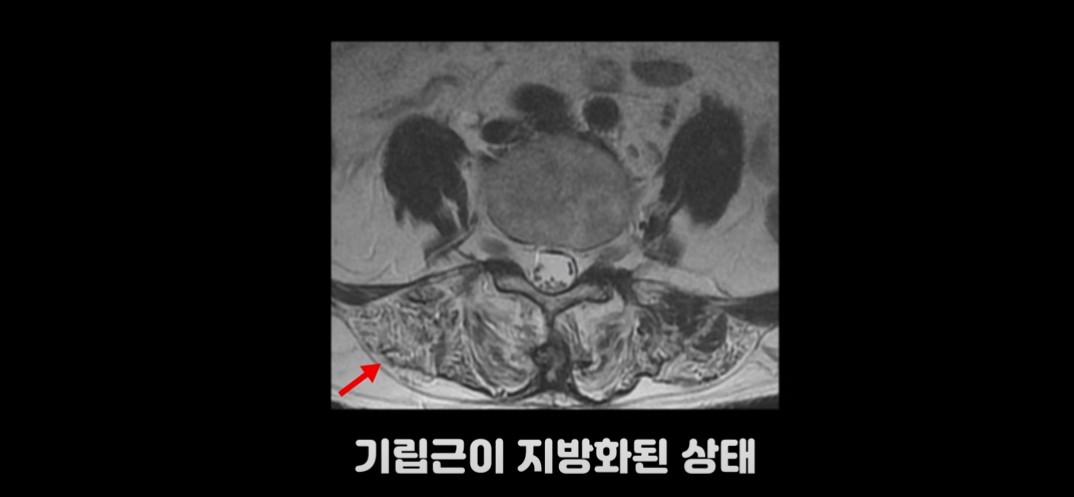

여기 허리가 많이 구부러지는 70세 이후 환자분의 MRI를 보시겠습니다.

이 환자분의 기립근을 보면 MRI상 어둡게 보여야 할 근육이 사진에서 보는 것 같이 하얗게 보입니다. 근육이 지방으로 변해 버린 겁니다. 또 근육의 크기도 위축되어 많이 작아져 있습니다.